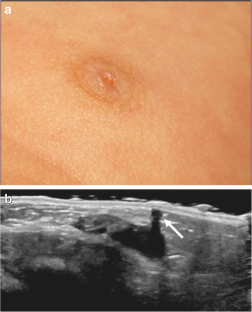

McHoney M, Munro F, Mackinlay G (2011) Mammary duct ectasia in children: report of a short series and review of the literature. Early Hum Dev 87:527–530

Acer T, Derbent M, Hiçsönmez A (2015) Bloody nipple discharge as a benign, self-limiting disorder in young children: a systematic review including two related case reports. J Pediatr Surg 50:1975–1982

Nascimento M, Portela A, Espada F, Fonseca M (2012, 2012) Bloody nipple discharge in infancy — report of two cases. BMJ Case Rep 2012:bcr2012006649